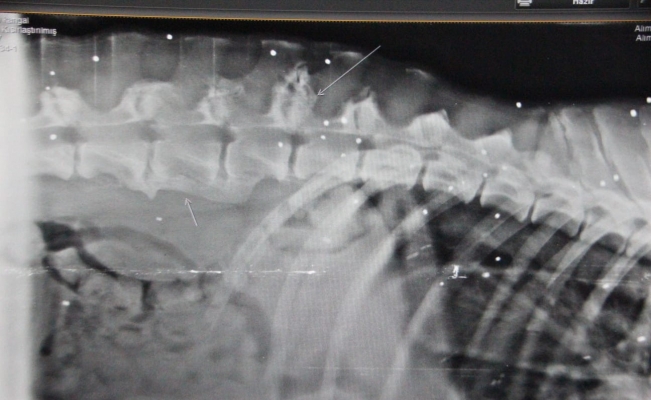

Edinilen bilgiye göre Bağla bölgesindeki bir sitede kangal cinsi 5-6 yaşlarındaki bir köpek, bitkin halde bulundu. İştahsızlık ve kusma şikayetleri bulunan ve dışarıdan bakıldığında bir yarası görünmeyen köpek, Turgutreis Bakımevi’ne gönderildi. Köpek, daha sonra ileri tetkik ve tedavi için Yalıkavak Terapi Veteriner Kliniğ’ine götürüldü. Yapılan kontrollerinde eklem hastalığı ve kan paraziti teşhis edilen köpeğe ayrıca röntgen çekildi. Çekilen röntgen sonucunda köpeğin vücudunda onlarca saçma ile yaşadığı ortaya çıktı. Ne zaman vurulduğu bilinmeyen köpeğin tedavisi sürüyor.